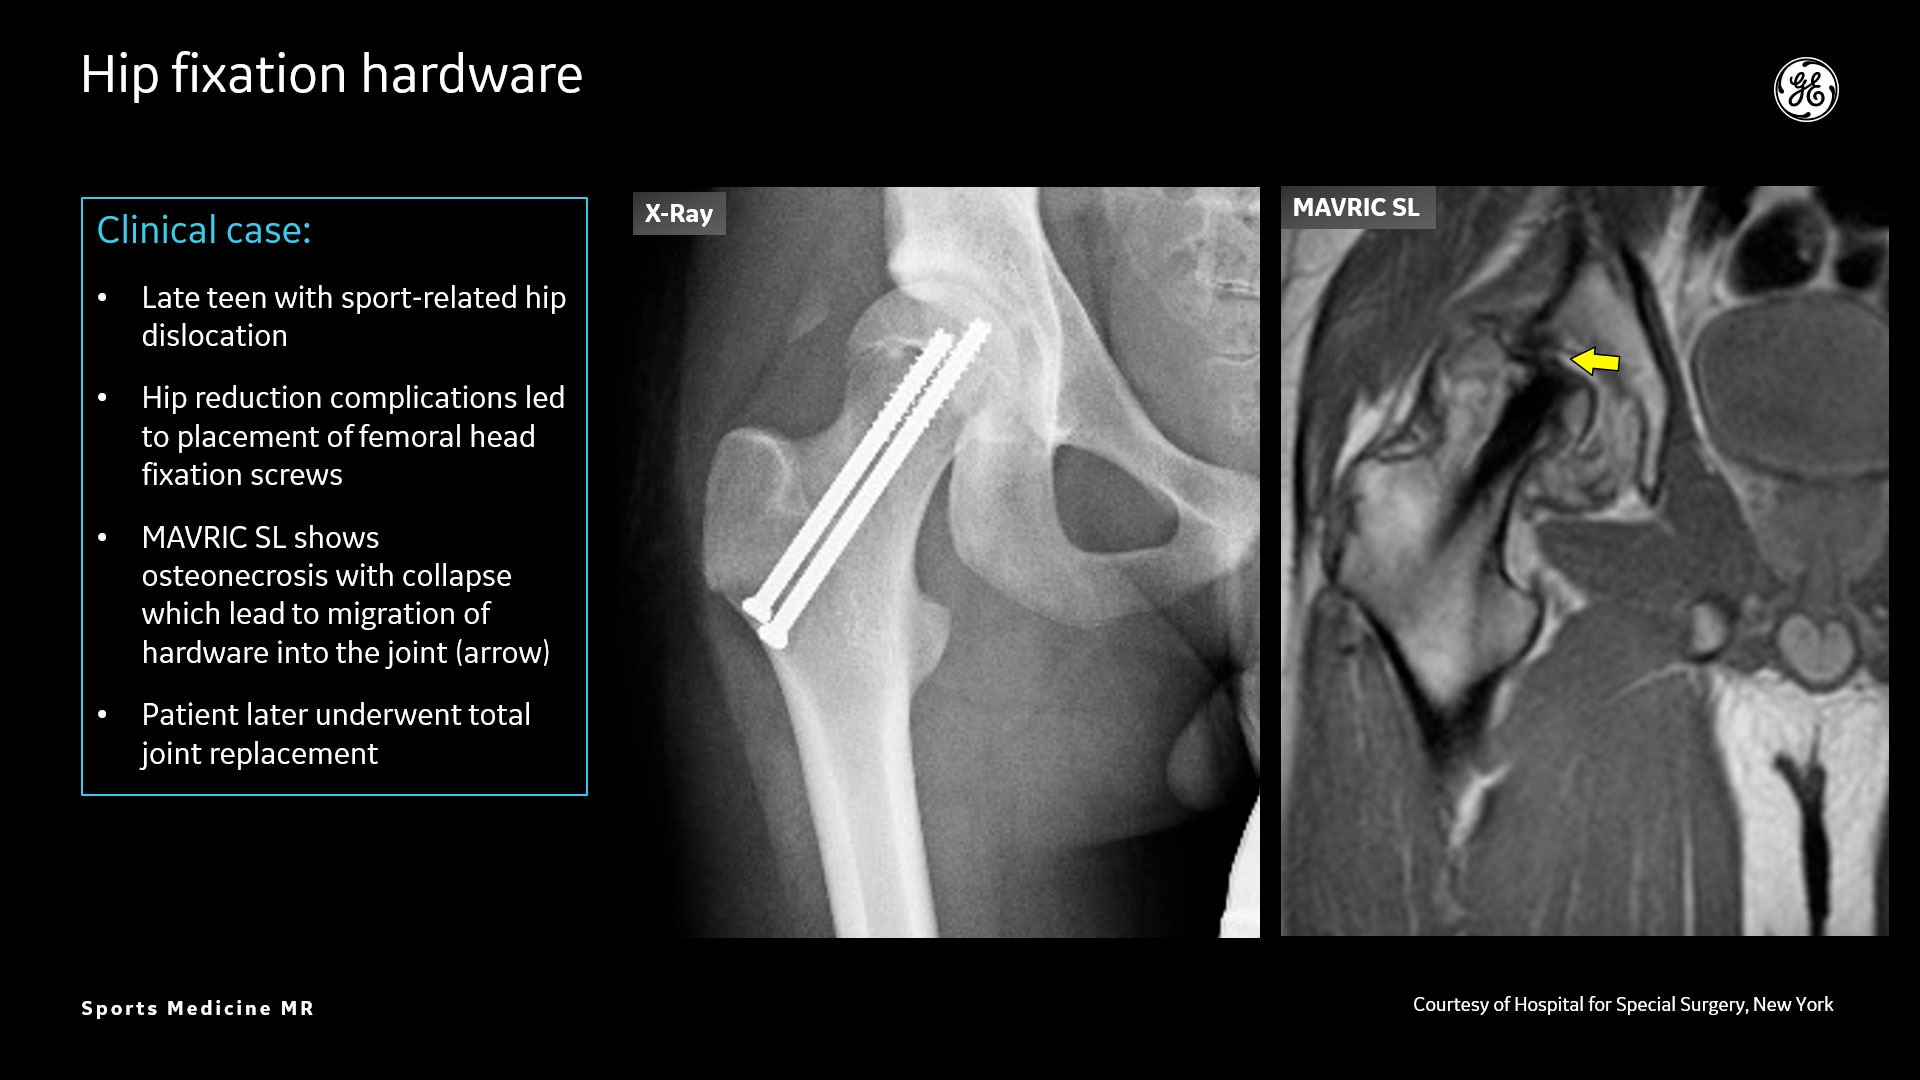

AIR™ Recon DL liefert hochauflösende Bilder mit erhöhtem SNR bei deutlich reduzierten Scanzeiten. Diese Technologie optimiert die Darstellung selbst kleiner Verletzungen wie Meniskus-, Labrum- und Bänderrisse. Die Verkürzung der Scanzeiten erhöht die Flexibilität für individuell abgestimmte MR-Protokolle mit einer zusätzlichen oZTEo-Sequenz für eine detaillierte Frakturbeurteilung.